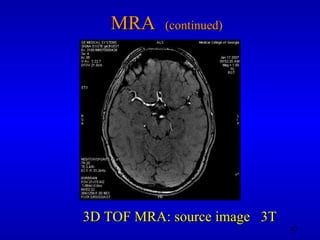

MRA  (continued) 3D TOF MRA: source image  3T

MRA (continued)3D TOF MRA: source image 3T